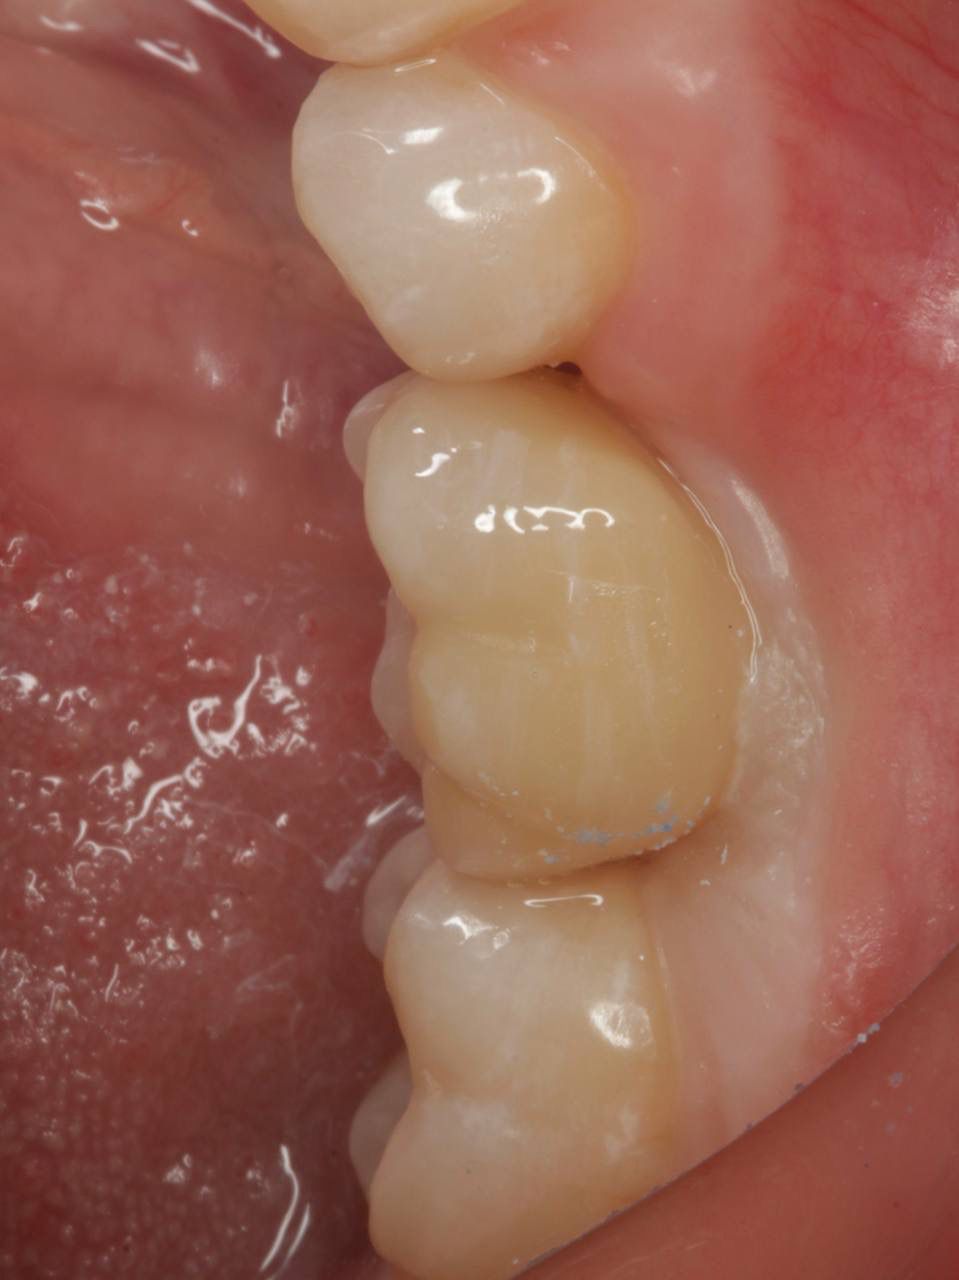

Одномоментная имплантация — Исламов Л.А.(10.11.2025)

Одномоментная имплантация системой Osstem(Ю. Корея), подшит трансплантат с бугра(для увеличения объема мягких тканей), установлен формирователь десны. Через 3 месяца установлена коронка из диоксида циркония на винтовой фиксации